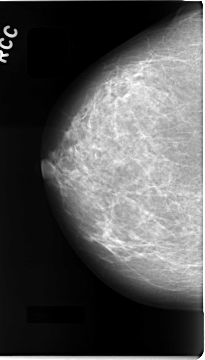

C_0059_1.RIGHT_CC

RIGHT_CC LINES 4680 PIXELS_PER_LINE 2656 BITS_PER_PIXEL 12 RESOLUTION 50 NON_OVERLAY